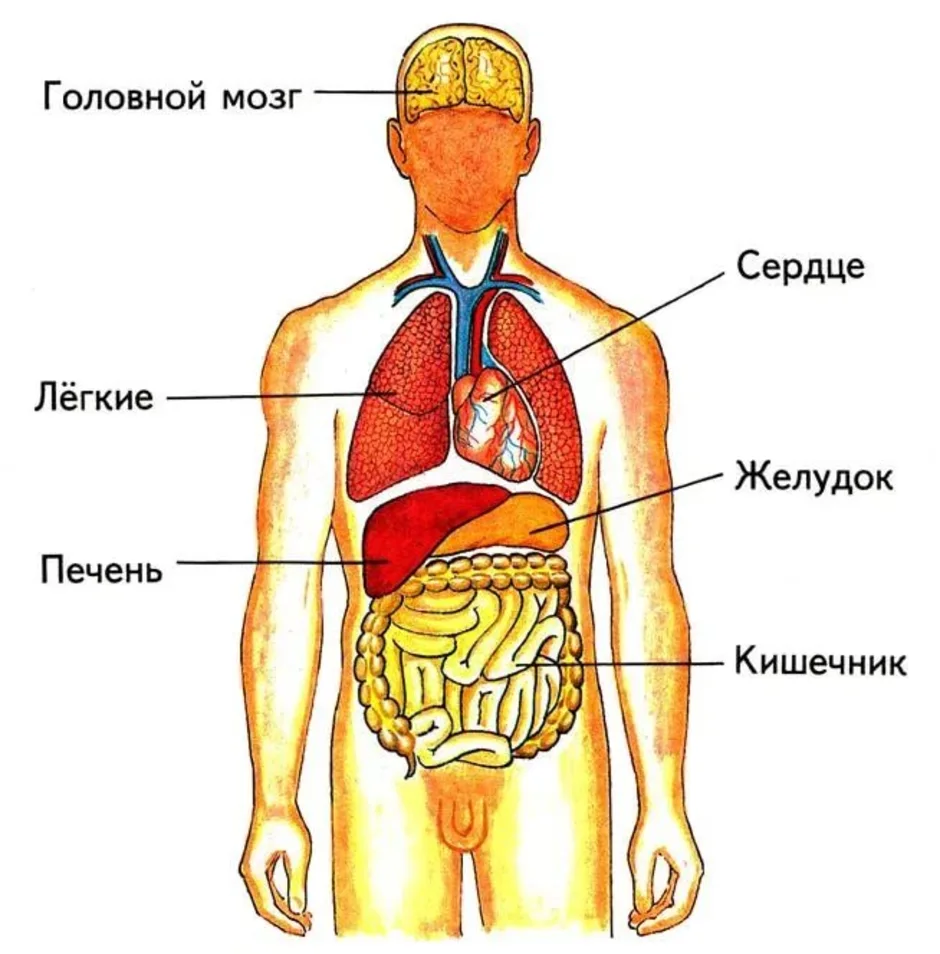

Изображения и визуализация внутренних органов человека